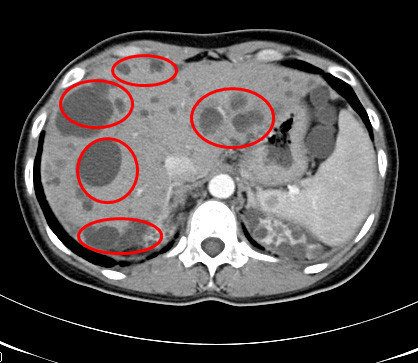

大约有10%左右的人都有肝囊肿,有些人一旦检查出肝囊肿,误认为这也是种瘤子,十分害怕,其实不对,肝囊肿不是肿瘤,是一种良性的囊性结构。 肝囊肿,通俗点说就是肝脏中的“水泡”。绝大多数的肝囊肿都是先天性的,即因先天发育的某些异常导致了肝囊肿形成。后天性的因素少有,如在牧区,如人们染上了包囊虫病,在肝脏中便会产生寄生虫性囊肿。外伤、炎症,甚至肿瘤也可以引起肝囊肿。囊肿可以是单发的,就只一个,小至0.2厘米;也可以多到十来个、几十个,甚至也可有一个是大至几十厘米的。多发性肝囊肿病人有时还合并其他内脏的囊肿,如伴发肾囊肿、肺囊肿及偶有胰囊肿、脾囊肿等。多囊肝的囊肿可满布肝脏,有些病人常以上腹肿块为首发症状,终末期出现腹水,门脉高压等肝功能不全的症候。肝囊肿一般是没有症状的。当囊肿长大到一定程度,可能会压迫胃肠道而引起症状,如上腹不适饱胀;也有因囊肿继发细菌感染而有腹痛、发热的。随着影象诊断学的发展及普及,尤其是B超已列为人群体格检查的常规之一,而B超对肝囊肿的检出率可达98%,所以发现本症的不少。在人们的心目中,囊肿是在肝脏上面长出来的一个肿瘤,尽管没有多大的症状,也很不放心,会不会变肝癌呢?肝囊肿常见的并发症是破裂出血、细菌感染、瘘及穿透,而罕见癌变。先天性肝囊肿是绝对不会癌变的。

肝囊肿是一种较常见的肝脏良性疾病,可分为寄生虫性、非寄生虫性和先天遗传性。

肝囊肿病因大多数系肝内小胆管发育障碍所致,单发性肝囊肿的发生是由于异位胆管造成。肝囊肿生长缓慢,所以可能长期或终生无症状,其临床表现也随囊肿位置、大小、数目以及有无压迫邻近器官和有无并发症而异。

肝囊肿与肿瘤是完全不同的两个概念。囊肿是液性占位,而肿瘤是实质性占位。一般说,在B超下,囊肿与肿瘤很易鉴别。应该警惕的是,肝囊肿与肝癌可合并存在,肝癌伴发肝囊肿并非罕见。因此,临床医生不要满足于肝囊肿的诊断?;褂κ笨瘫3侄愿伟┑木栊?,为此,发现有肝囊肿者,一不要忘记检测血AFP,因为60%-70%的原发性肝癌患者AFP升高。二是应到正规医院或找有经验医生行超声波检查,必要时可加作CT扫描检查。